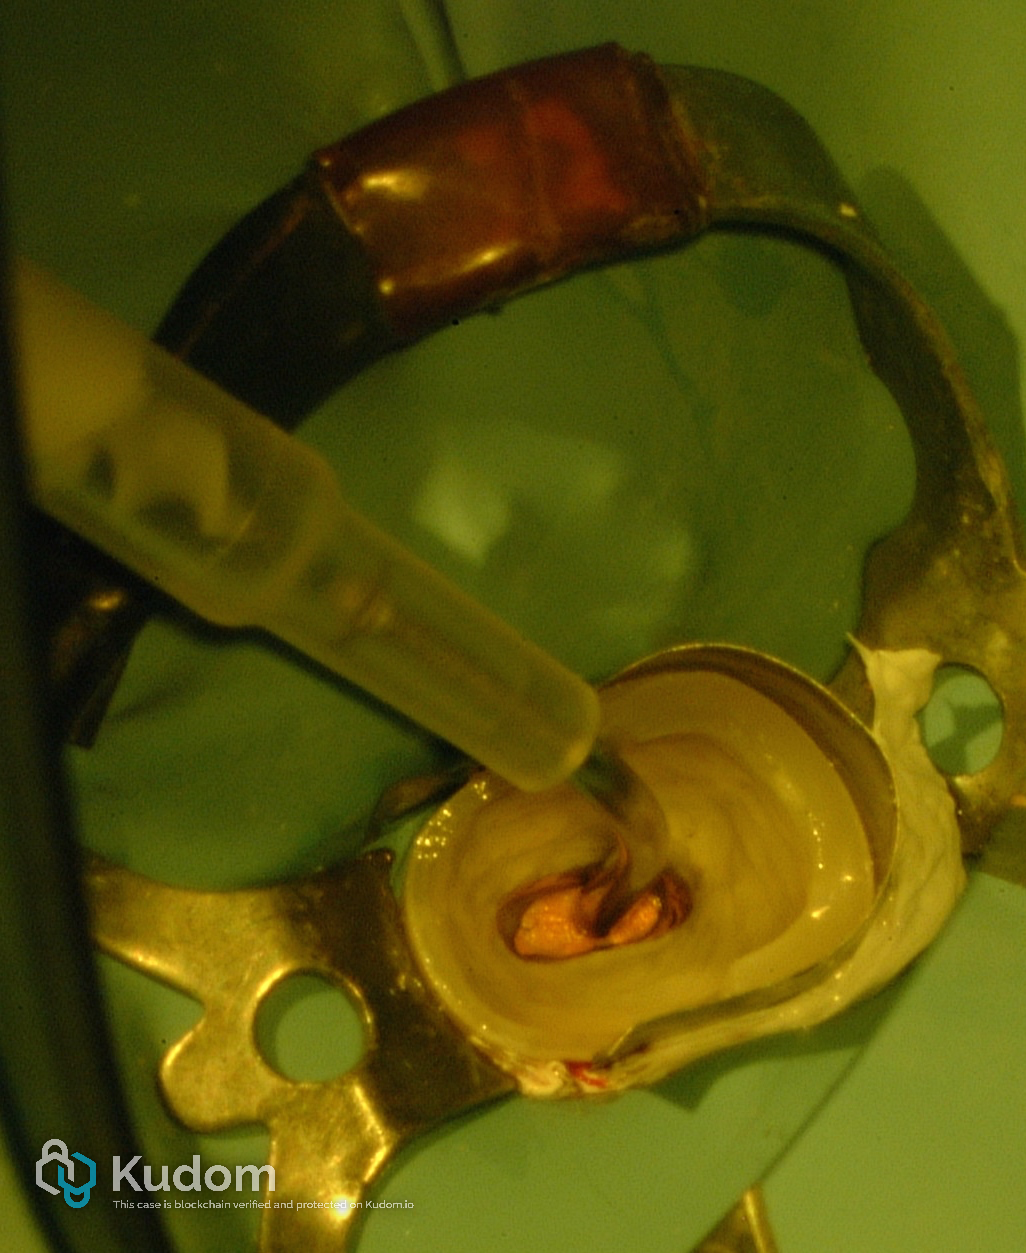

Following endodontic treatment, the post space was prepared to receive a fiber post

Fig. 4

An HI-REM POST (Overfibers), characterized by its elliptical shape, was selected to enhance adaptation to the canal’s original middle-third morphology.

Fig. 5